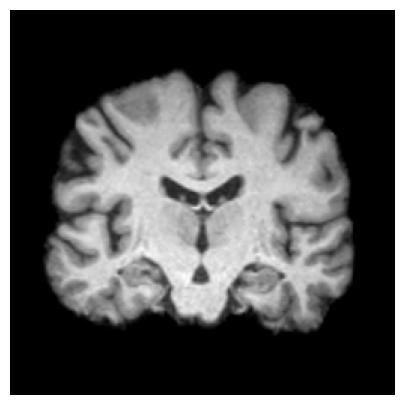

4.3.2 ADNI

We consider two groups constructed from the ADNI dataset based on hippocampal volume, a well-established neuroimaging biomarker of Alzheimer’s disease–related neurodegeneration. Each group includes 918 2D slices. Subjects exhibiting reduced hippocampal volume indicative of hippocampal atrophy are assigned to Group 1, while subjects with preserved hippocampal volume form Group 2. This stratification induces group differences associated with disease-relevant anatomical variation and provides a clinically meaningful setting for evaluating whether the proposed feature-level explanations highlight brain regions known to be implicated in Alzheimer’s disease/cognitive impairment.

We use a ResNet-50 encoder pretrained on the UK Biobank dataset, predicting the age of brains, and adapt this pretrained model using a linear probing strategy on the ADNI dataset. Specifically, we train a logistic regression layer on top of the frozen encoder to predict group membership, while keeping all encoder parameters fixed. After training, the linear head is discarded, and the frozen encoder is used to extract embeddings for two-sample testing and for generating feature-level explanations. We apply the proposed feature-level explanation method to individual MRI scans and assess whether the resulting attributions align with known disease-related neuroanatomical patterns.

Results.

Figure 7 indicates the qualitative results. Our explainability method consistently highlights the hippocampal and medial temporal lobe regions, and the resulting heatmaps show strong correspondence with areas affected by hippocampal atrophy. These results supports that the identified regions align with established AD biomarkers.